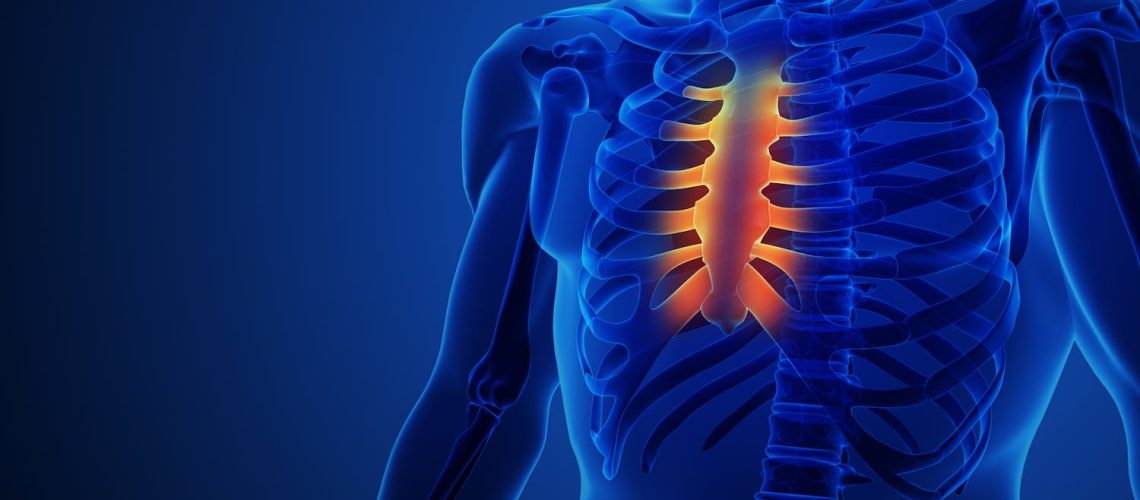

Le sternum joue un rôle discret, mais central dans la structure du thorax et dans la protection de nos organes vitaux. Comment fonctionne-t-il ? Et pourquoi peut-il faire mal, parfois ?

Le sternum joue un rôle discret, mais central dans la structure du thorax et dans la protection de nos organes vitaux. Comment fonctionne-t-il ? Et pourquoi peut-il faire mal, parfois ?  Read MoreSanté Magazine